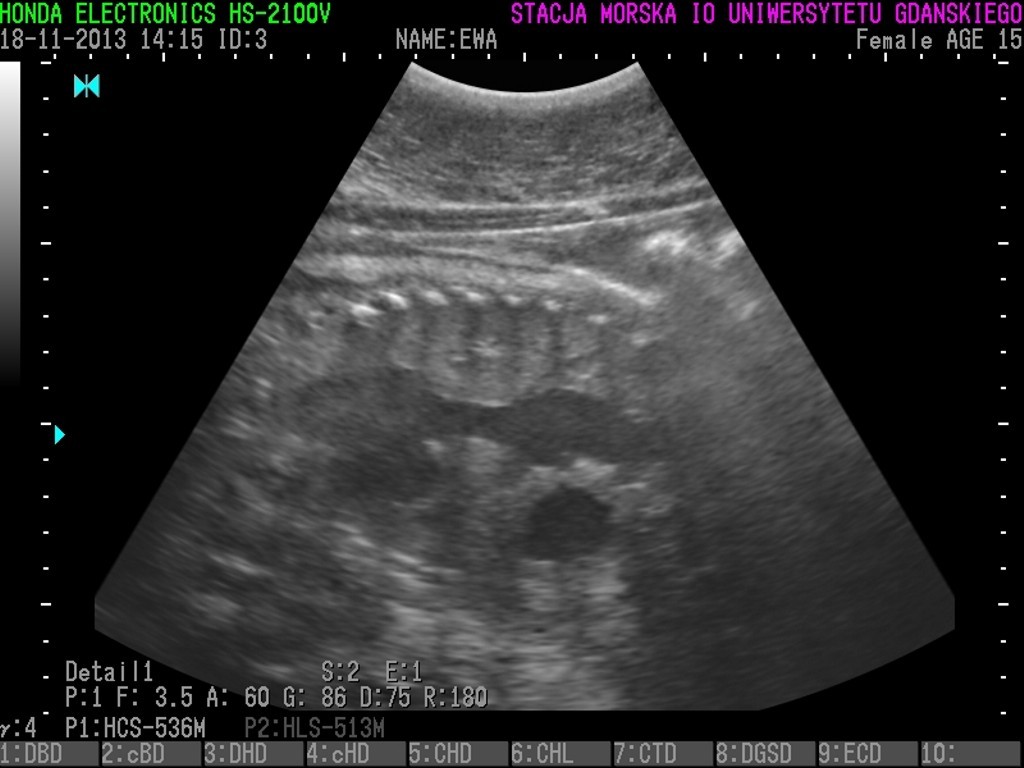

Unda Marina, Ewa i Ania urodzą? Badania 3 fok wskazały, że znajdują się w zaawansowanej ciąży i jeśli nie wydarzą się żadne nieprzewidziane okoliczności, na początku marca możemy spodziewać się trzech młodych osobników.

Dzięki specjalistycznemu sprzętowi, zakupionemu przy wsparciu WWF wiadomo, że focza ciąża przebiega obecnie bez większych problemów. Wkrótce będziemy mogli poznać również płeć fok.